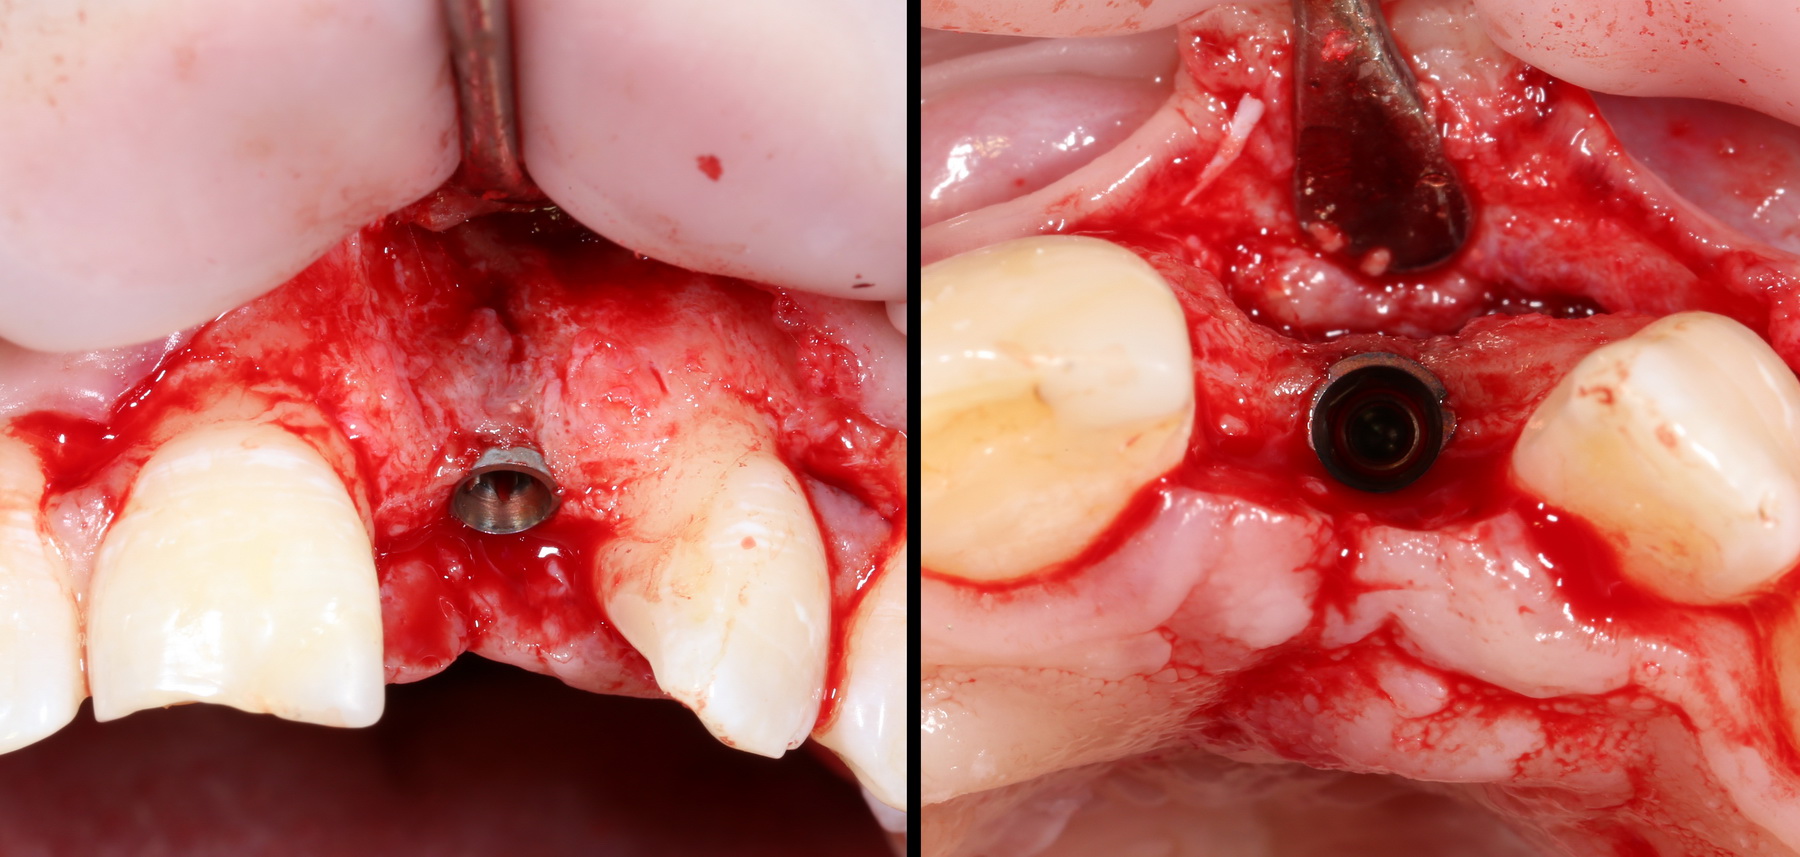

Вернемся к нашему клиническому случаю. Мы уже поставили импланты с расчетом на будущую высоту альвеолярного гребня и положение будущих зубов:

И, если в предыдущей части мы рассматривали ситуацию, когда принимающее ложе имеет относительно простой рельеф, и у нас не возникло сложностей с адаптацией аутоблока, то в случае, рассматриваемом сегодня, нормальная и точная адаптация крупного костного фрагмента, практически, невозможна. Именно поэтому мы решили использовать направленную костную регенерацию (НКР), поскольку с адаптацией тестообразного по консистенции графта проблем, обычно, никогда не бывает. Как, например, в этом случае:

С помощью него мы «достраиваем» недостающую часть альвеолярного гребня, полностью перекрывая импланты. Напомню, что субкрестальные Ankylos Dentsply Implants вполне допускают такой подход.

Следующая задача — найти импланты, которые полностью заросли костной тканью:

Ставим на них формирователи десны, ушиваем рану с расчетом на вторичное натяжение.